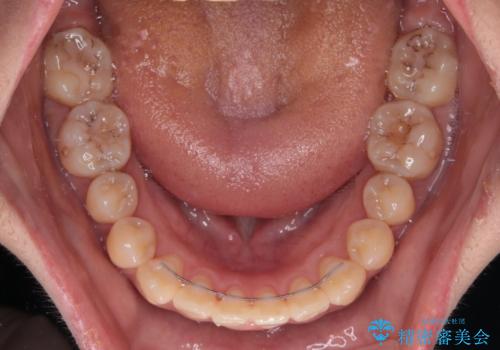

治療開始直後に上顎前歯に激しい痛みが発現し、矯正治療を休んだり、マウスピースの装着時間を短くしたりと工夫をしましたが、残念ながら治療途中で失活していることが分かりました。

矯正治療の途中で前歯の根管治療とオールセラミッククラウンによる補綴治療を行い、その後インビザライン1セットを用いて細かい部分を仕上げました。